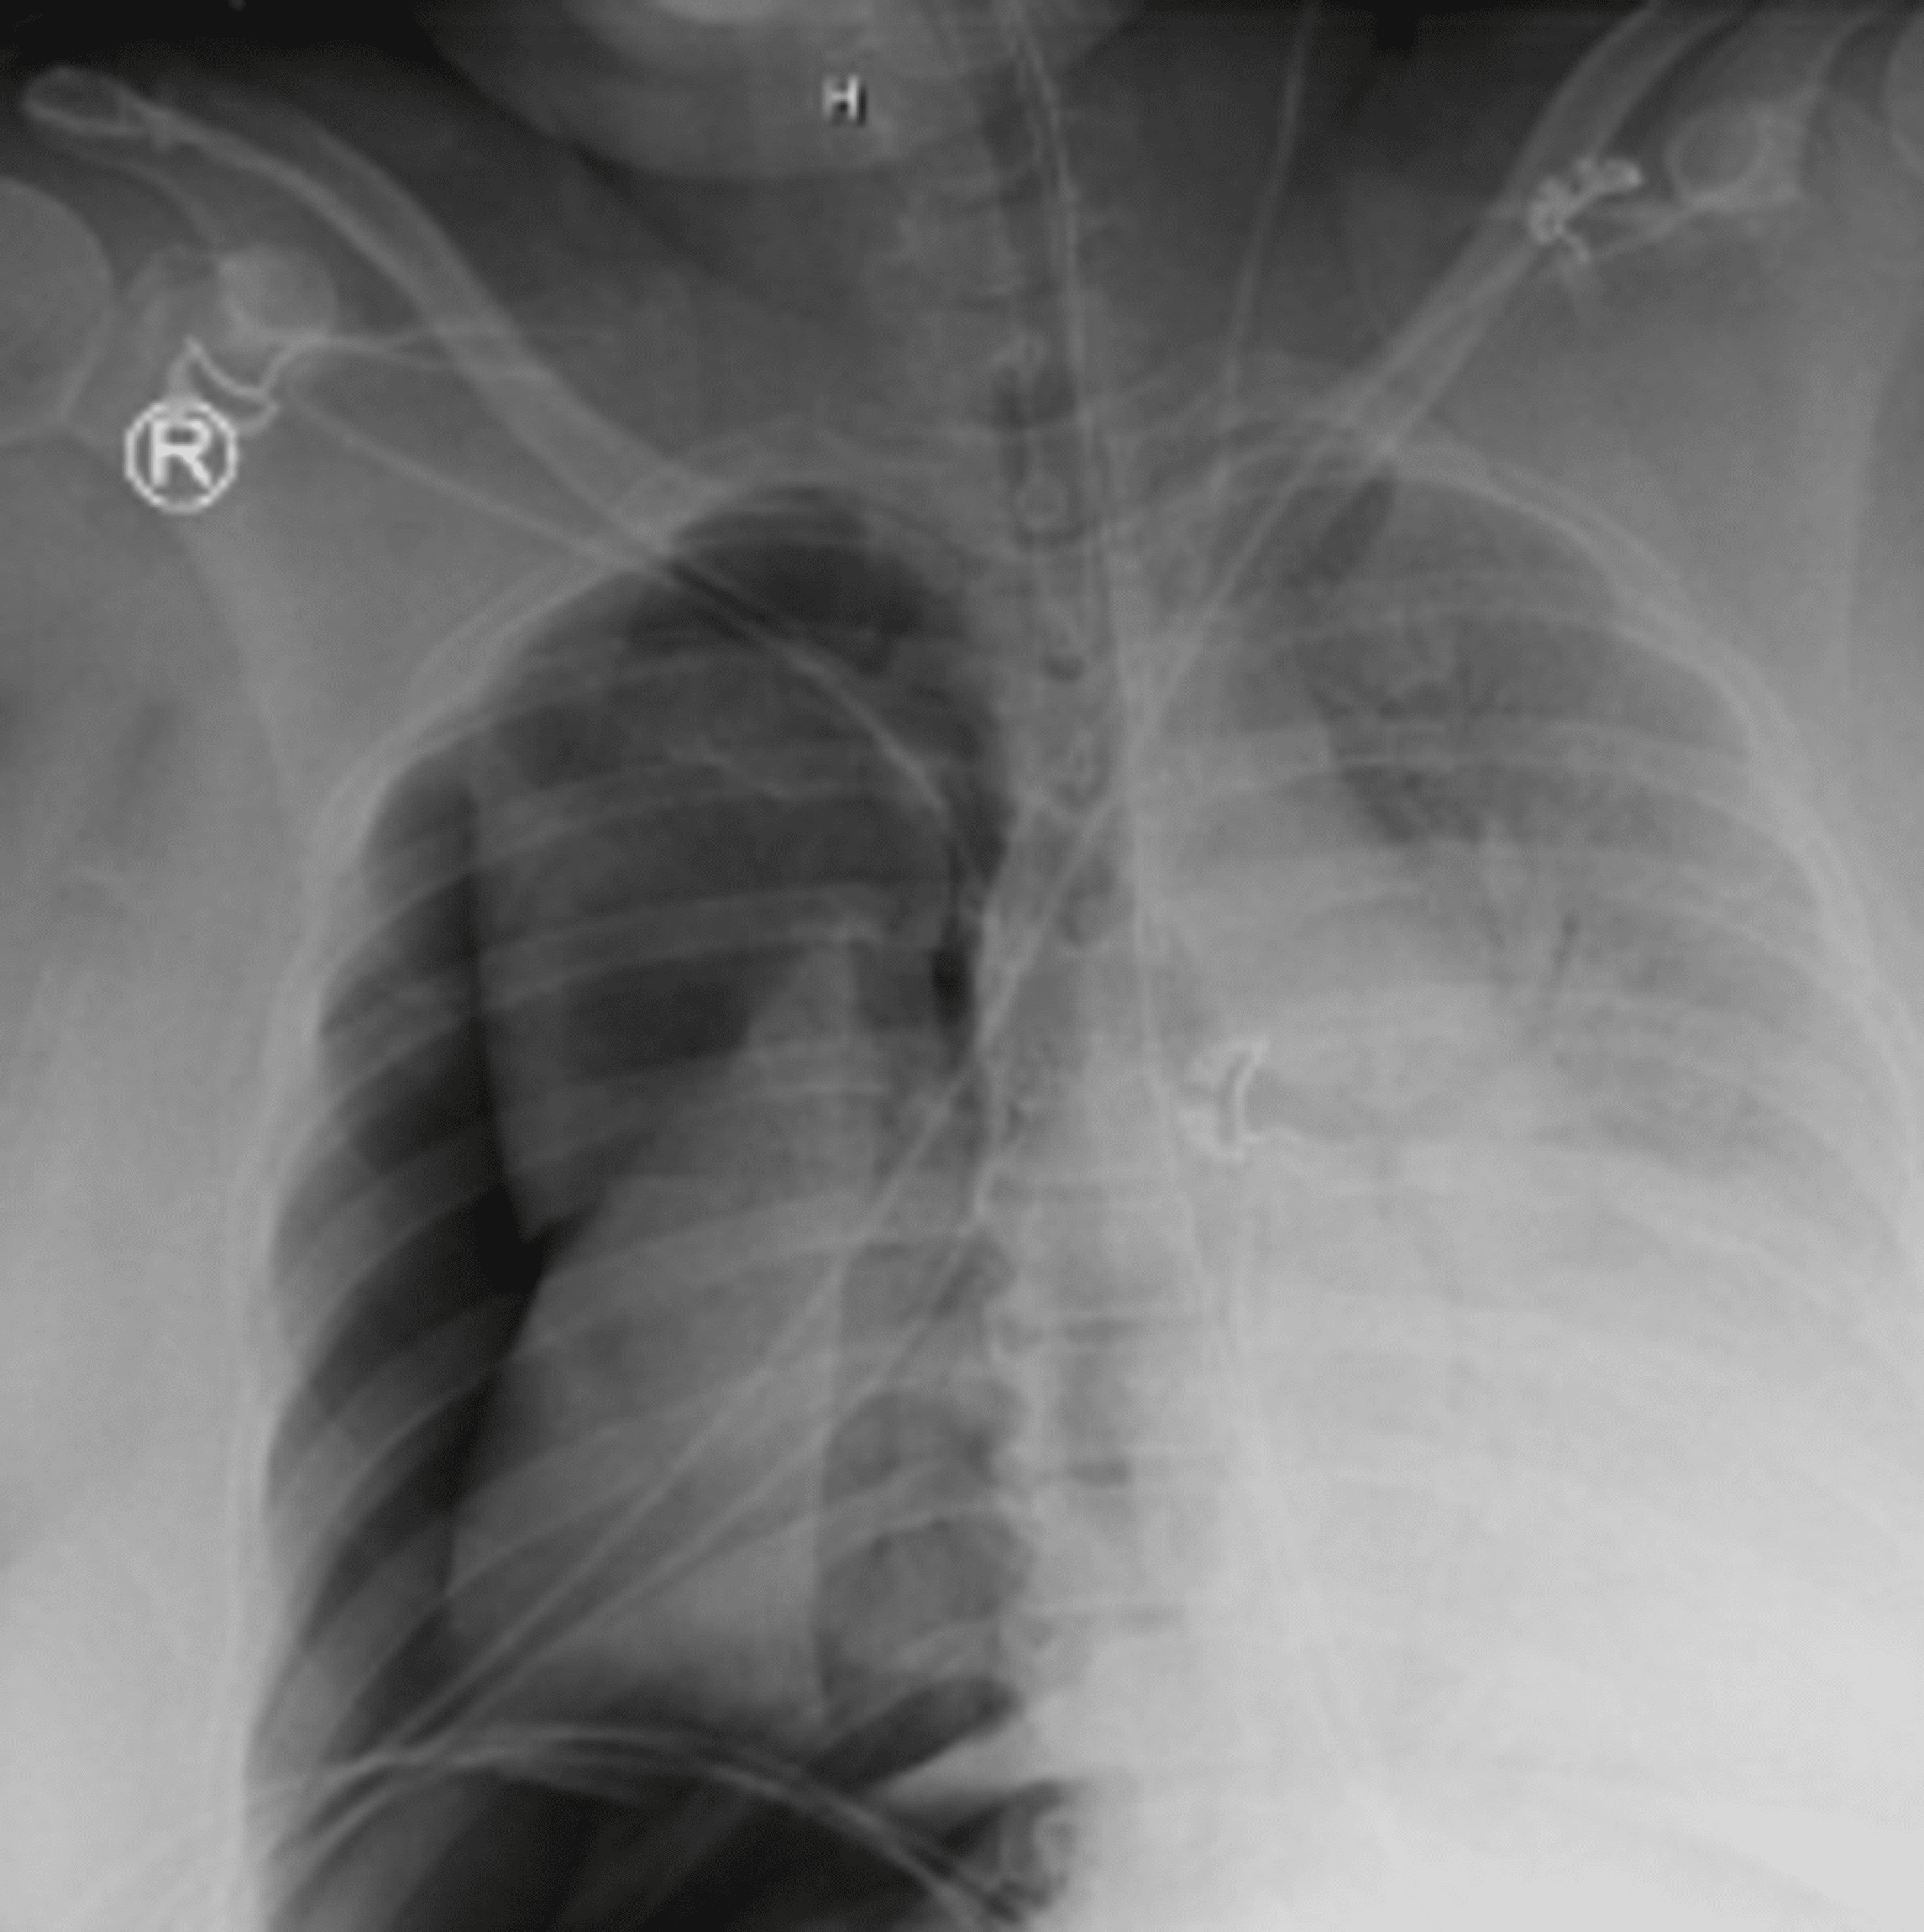

Barotrauma In Mechanical Ventilation . Web there is no single strategy to prevent pulmonary barotrauma on patients on mechanical ventilation. The most efficient mechanism that. Web pulmonary barotrauma was the most common complication of mechanical ventilation, but modern strategies have. Web pulmonary barotrauma can complicate mechanical ventilation. It is most often due to alveolar rupture resulting in. Web pulmonary barotrauma is a complication of mechanical ventilation and has correlations with increased morbidity.

Web pulmonary barotrauma is a complication of mechanical ventilation and has correlations with increased morbidity. The most efficient mechanism that. Web pulmonary barotrauma was the most common complication of mechanical ventilation, but modern strategies have. Web there is no single strategy to prevent pulmonary barotrauma on patients on mechanical ventilation. Web pulmonary barotrauma can complicate mechanical ventilation. It is most often due to alveolar rupture resulting in.